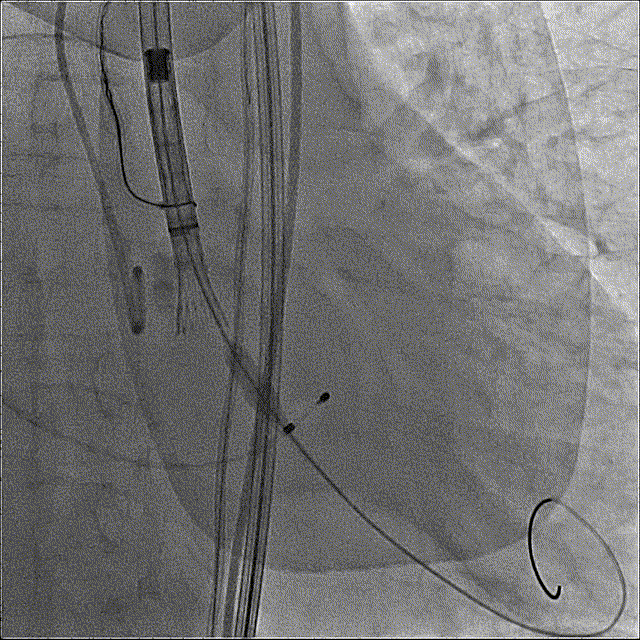

猪尾中部初始定位

初始释放定位